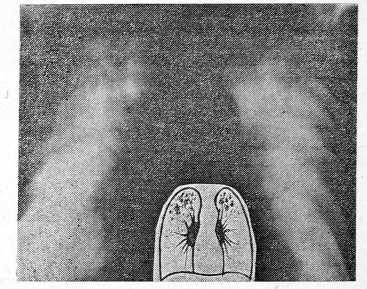

- У второй группы больных наблюдались множественные метастазы, среди которых по размеру можно выделить 2 варианта: мелкие (до 1 см в диаметре) и крупные. По существу, они являются этапами развития одного процесса, и если при диссеминированном карциноматозе значительный рост очагов констатируется не всегда из-за быстрой гибели больных, то при множественных метастазах его можно видеть постоянно. Выделение этой группы целесообразно потому, что общей, объединяющей чертой является сравнительно небольшое количество очаговых теней — от 2—3 до нескольких десятков. Поэтому спутать их с диссеминированным туберкулезом практически невозможно. При подобном рентгенологическом синдроме кроме рака можно скорее предположить множественные метастазы альвеококка, цистицеркоз, пневмонию и множественные туберкулемы (рис. 5, 6).

Рис. 5. Рентгенограмма больного В., 42 лет. Определяется левосторонний плевропневмосклероз — исход деструктивного туберкулеза, леченного в 1957 г. искусственным пневмотораксом. Клинически здоров.

Рис. 6. Рентгенограмма больного В., 42 через год, выявлены множественные округлые тени диаметром до 2,5 см на всем протяжении обоих легких.

Рентгенологическая картина характерна для множественных метастазов опухоли, первичная локализация которой при дальнейшем исследовании была обнаружена в кишечнике.